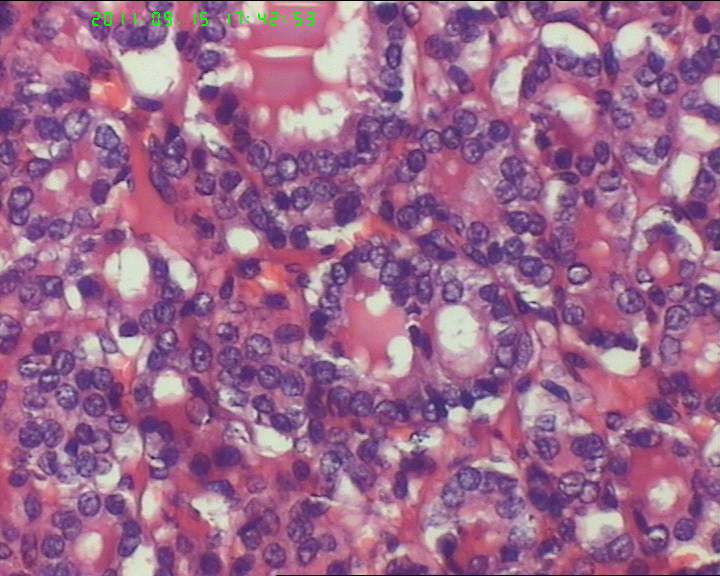

38岁女性甲状腺,腺瘤?滤泡癌?

甲状腺右下极一肿物,3*3大小,切面灰红实性质韧,可见部分包膜,一侧可见一空腔,未见内容物。

38岁女性甲状腺,腺瘤?滤泡癌?图2

名称:图2

描述:20110915-2.jpg.jpg